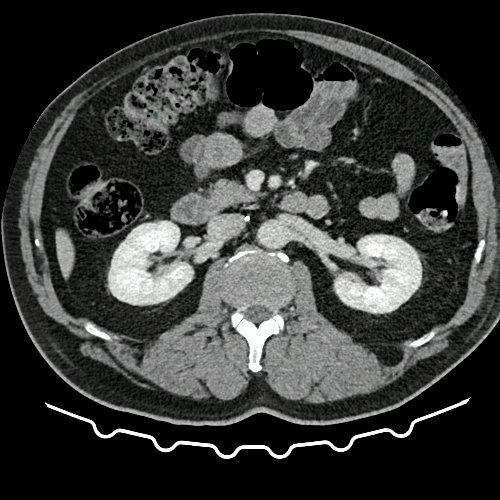

• TAC de abdomen y pelvis con contraste EV (Día 10): El hígado es de forma, tamaño y situación habituales. Su superficie es lisa, y sus bordes son agudos. No presenta alteraciones densitométricas ni efectos de masa focales. La vía biliar intra y extrahepática es de calibre conservado. La vesícula biliar es de forma, tamaño y situación normales, sin imágenes que sugieran la presencia de litiasis. Tener en cuenta que este método puede pasar por alto litiasis colesterínicas. El bazo es de forma, tamaño y situación normales. El eje esplenoportal es de calibre y trayecto conservado. El páncreas es de características normales. El conducto de Wirsung es de calibre conservado. Las glándulas adrenales son normales. Ambos riñones son de forma, tamaño y situación habituales. Sin evidencia de alteraciones calicopiélicas ni ureterales. Quistes simples corticales en riñón izquierdo, el mayor de ellos en polo superior, que mide 16 mm. Discreta reticulación de la grasa perirrenal bilateral. La aorta, las arterias ilíacas primitivas, internas, externas y femorales, son de calibre y trayecto conservado. La vena cava inferior y las venas ilíacas primitivas, internas, externas y femorales son de calibre y trayecto conservados. Filtro de vena cava inferior infrayacente a venas renales. No se observan adenomegalias intraperitoneales, retroperitoneales, ilíacas ni inguinales. No se observan alteraciones a nivel del tracto gastrointestinal. Abundante contenido de materia fecal en el colon. Vejiga con escasa repleción. La próstata y las vesículas seminales son de características normales. No se observa líquido libre ni neumoperitoneo Presenta aumento del diámetro de la raíz del muslo izquierdo con respecto a su contralateral, asociado a edema de los tejidos blandos superficiales. Reticulación de los tejidos blandos de la región inguinal izquierda, de mayor jerarquía que en estudio anterior, con tendencia a coleccionar. Además se observan ganglios locorregionales aumentados en número y tamaño sin alcanzar rango megálico. Se observa inmediatamente infrayacente a los antes mencionado, un área hiperdensa que realza en fase venosa, con centro hipodenso, que mide 2.2 cm x 1.4 cm, ya visualizado en tomografía previa, sin cambios. Calcificaciones en conducto inguinal bilateral. Hidrocele bilateral. Marcados cambios artrodegenerativos de la columna lumbosacra y coxo-femorales.

TAC de tórax, abdomen y pelvis con contraste EV (Día 10) Corte axial